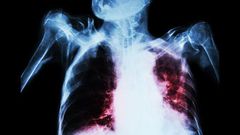

More investment is needed to beat tuberculosis, the joint most deadly infectious disease in the world, a coalition of health agencies has said.

TB is the most deadly infectious disease, alongside HIV, figures show.

But most cases of TB can be treated with first-choice antibiotics, and the WHO has called the death rate unacceptable.